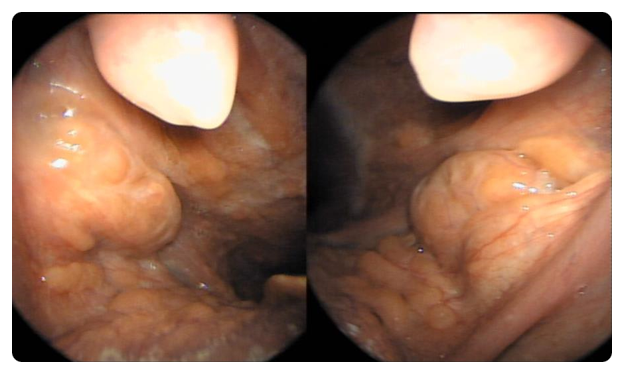

편도의 크기는 크지도 않았고 검사 당시에는 특별히 눈에 띄는 결석도 없었습니다. 크기 1단계로 작은 편입니다.

그렇게 많은 결석은 모두 어디로 갔을까요? 그리고 어디서 나타날까요?사실 눈에 보이는 결석만이 전부는 아닙니다.사실 눈에 보이는 결석만이 전부는 아닙니다. 결석은 편도의 더 깊은 곳에도 있습니다. 또한 편도의 최심부인 편도 중앙에서도 편도 결석이 자랍니다. 결석 제거를 위한 부분적인 편도절제술로 재발이 많은 이유가 그 때문입니다. 바깥쪽 편도 봉투를 자른 곳에서 안쪽에서 다시 바로 나옵니다.

이 환자의 경우 심부 60% 정도에 이르기까지 편도 내에 다량의 결석이 존재하고 있었습니다. 수술하면서 편도를 잡고 누를 때 상당한 양의 편도 결석이 밖으로 튀어나왔습니다.